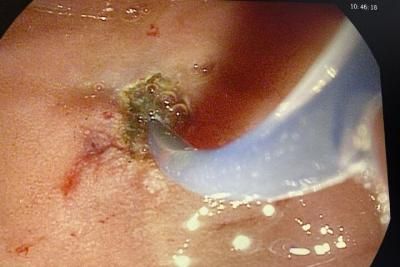

Хирурги Саратовской областной клинической больницы впервые провели высокотехнологичную операцию по удалению камней из протоков поджелудочной железы. Как сообщается в телеграм-канале лечебного учреждения, на операционном столе оказался молодой пациент с редкой патологией — калькулезным панкреатитом.

" При этом заболевании пациент испытывает сильные боли, так как в протоке поджелудочной железы образуются камни, что в итоге может привести к некрозу органа и даже летальному исходу ", — сообщают медики больницы.

Заведующий эндоскопическим отделением Сергей Скопец пояснил, что было принято решение сделать операцию в два приема с разницей в неделю. Во время первого этапа железу разрезали и установили в протоки стент. Через 7 дней камни удалили. По словам Скопца, сложность выполнения такой процедуры в том, что размер железы маленький, как и ее протоков, диаметр которых составляет 2-3 мм. Пациент перенес операцию хорошо и пошел на поправку.

Фото - Саратовская областная клиническая больница